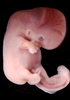

Carnegie Stage 18 (44 post-ovulatory days)

Most embryos at stage 18 are approximately 44 postovulatory days old and measure 13-17 mm in length. Distinguishing criteria for this stage include cervical and lumbar flexures, distinct notching in the hand plate, the first appearance of the elbow, eyelid folds may appear in more advanced specimens, and auricular hillocks begin to form distinct parts of the external ear.